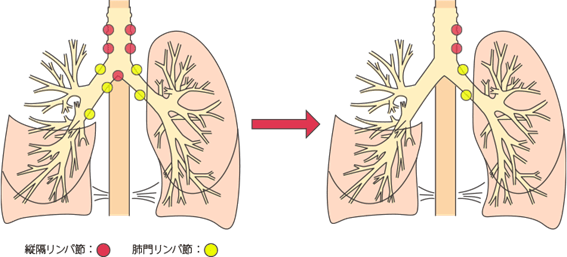

肺がんがリンパ節に転移した場合は

人間の体には、血管と同じように全身をめぐるリンパ系というネットワークがあります。リンパ系は、体中に張りめぐらされたリンパ管と、リンパ管の集まるリンパ節からできており、細菌やがん細胞をやっつける免疫機能を担っています。

がんが大きくなって近くのリンパ節に広がると、がん細胞がリンパ管を通って、別のリンパ節へ転移するリンパ行性転移が起こります。肺には多くのリンパ節があるため、肺がんはリンパ行性転移を起こしやすいがんといえます。

リンパ節転移が起こると、リンパ節が腫れて周囲の神経や器官を圧迫するため、いろいろな症状が起こります。

リンパ節への転移とステージ・症状

がんの部位に応じて転移しやすいリンパ節がグループ化されており、それを所属リンパ節といいます。

肺がんでは、肺門(肺の入り口周辺)リンパ節、肺内(肺の中)リンパ節、縦隔(左右の肺に挟まれた空間)リンパ節という3つのグループに分かれます。

所属リンパ節への転移の段階はN因子(NX、N0、N1、N2、N3)で表され、病期(ステージ)を決める要素の一つです。数字が大きくなるほど、転移の範囲が広がっていることを示します。

肺がんのリンパ節転移をN因子で表すと、

NXは、所属リンパ節に転移があるかどうか評価できないことです。所属リンパ節がすでに摘出されているときなどにNXとなります。

N0は、所属リンパ節に転移がないことです。

N1は、最初にできたがん(原発巣)と同じ側の気管支周囲や肺門または肺内リンパ節に転移があることです。

N2は、原発巣と同じ側の縦隔リンパ節または気管支が分かれる部位のリンパ節に転移があることです。

N3は、原発巣とは反対側の縦隔リンパ節や肺門リンパ節または鎖骨上のリンパ節、首の付け根にあるリンパ節に転移があることです。

肺の入り口や気管支周辺のリンパ節に転移があると、咳がでてくることがあります。

気管支前リンパ節に転移が起こると、上大静脈が圧迫されるので上半身のむくみや息切れ、頭痛、めまい、眠気などの上大静脈症候群があらわれることがあります。

左側の気管支リンパ節に転移が起こると、かすれ声が起こることがあります。

リンパ節転移があると、病期(ステージ)はII期以上と判定されます。

リンパ節は他の部位と比べて転移を起こしやすいため、原発巣を手術で取り除くとき、同時に、所属リンパ節の切除(リンパ節郭清)も行うのが一般的です。リンパ節をどの程度切除するか(リンパ節郭清度)は原発巣の部位などによって決まります。

リンパ節転移を起こしていても、原発巣とともにリンパ節転移をすべて切除できれば、再発・転移の可能性を低下させることができます。